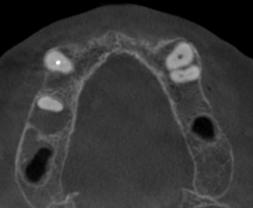

ABSTRACT

Systemic Lupus Erythematosus (SLE) is an autoimmune disease in which organs, tissues and cells are damaged by the exaggerated response of T cells and B cells, loss of immune tolerance against non-specific antigens of the organism. Lupus Enteritis (LE) is defined as vasculitis or inflammation of the small intestine that is diagnosed with the support of imaging and/or biopsy findings. Intestinal pneumatosis (PI) is a rare disease characterized by the presence of intramural gas in the gastrointestinal tract, associated with various clinical conditions, such as pulmonary diseases, gastrointestinal diseases and traumatic injuries, as well as autoimmune disorders.

A bibliographic search was carried out in databases such as PubMed, Nature, Elsevier and Google Scholar, with keywords such as “intestinal pneumatosis” and “lupus enteritis”.

Case presentation: Female patient with a history of surgery for intestinal obstruction, then returned due to a clinical picture of more or less 6 days, in poor general condition with hypotension 80/50 mmHg that did not improve with the administration of crystalloids, for which admission to the Intensive Care Unit (ICU) is indicated, with the need for vasopressors, interconsultation with surgery is carried out where it is decided to perform an exploratory laparoscopy, ruling out intestinal vascular compromise, after starting corticosteroids, the patient shows improvement and is discharged to the general ward in good condition and later home discharge.

Conclusion: Intestinal pneumatosis due to lupus enteritis is one of the rare manifestations with non-specific symptoms where prompt diagnosis and treatment is required. Giving a good response to corticosteroids and avoiding unnecessary surgical interventions.

Key words: Intestinal pneumatosis, lupus erythematosus, lupus enteritis,

INTRODUCCIÓN

El Lupus Eritematoso Sistémico (LES) es una enfermedad autoinmunitaria en la cual los órganos, tejidos y células se dañan por la respuesta exagerada de las células T y células B, perdida de la tolerancia inmune contra antígenos no específicos del organismo (1). La producción y eliminación defectuosa de anticuerpos, también depósitos de complejos autoinmunes, complemento y activación de citocinas (1), permiten el debut con las manifestaciones clínicas con la presencia de un 95 % de compromiso musculo esquelético, un 80 % cutáneas y con menos frecuencia las digestivas, 40 % (3), siendo así que la última que se menciona no forma parte del criterio diagnóstico

por la infrecuencia de los síntomas; la afectación gastrointestinal es una queja común que se observa en el 40 a 60 % de los pacientes con LES; se han descrito manifestaciones gastrointestinales clínicamente reconocidas en el 8 al 10% de los pacientes; por otro lado, los estudios de autopsia, informan hallazgos de compromiso gastrointestinal en el 60 a 70 % de los pacientes lo que sugiere un compromiso subclínico o no reconocido (11).

La Enteritis Lúpica (EL) es definida como una vasculitis o inflamación del intestino delgado con apoyo de hallazgos de imagen y/o biopsia; en la cual la tomografía es el examen de elección que nos muestra una mayor visibilidad de los vasos